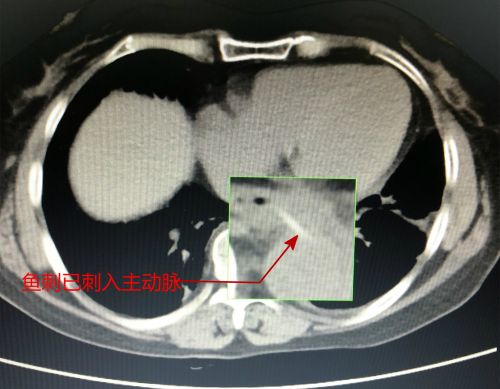

ct显示,鱼刺已经刺入胸主动脉。

好在血管没有被扎破,只是形成了血肿。

57岁的张女士是湖南安化县人,2月10日吃饭时不小心误吞鱼刺,当时就有针刺的感觉,尝试了吞饭团、喝醋等方法后仍然胸痛难忍。到当地捷克论坛 就诊发现,张女士的食道里布满鲜血,却找不到鱼刺。进一步检查发现,鱼刺已刺破食道进入胸主动脉!幸运的是,鱼刺尚未刺破胸主动脉这一人体最大的动脉,只是形成一个血肿。但随着食道的蠕动或肢体运动,鱼刺随时可能扎破胸主动脉,引起大出血。由于胸主动脉是人体最粗大的动脉血管,血管压力很高,一旦形成破口,出血将呈喷射状,如果3分钟内无法成功止血,患者将有生命危险。